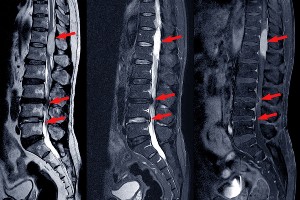

脊柱管狭窄

脊柱管的变窄,可能会对脊髓或神经施加压力,引起疼痛和不适。